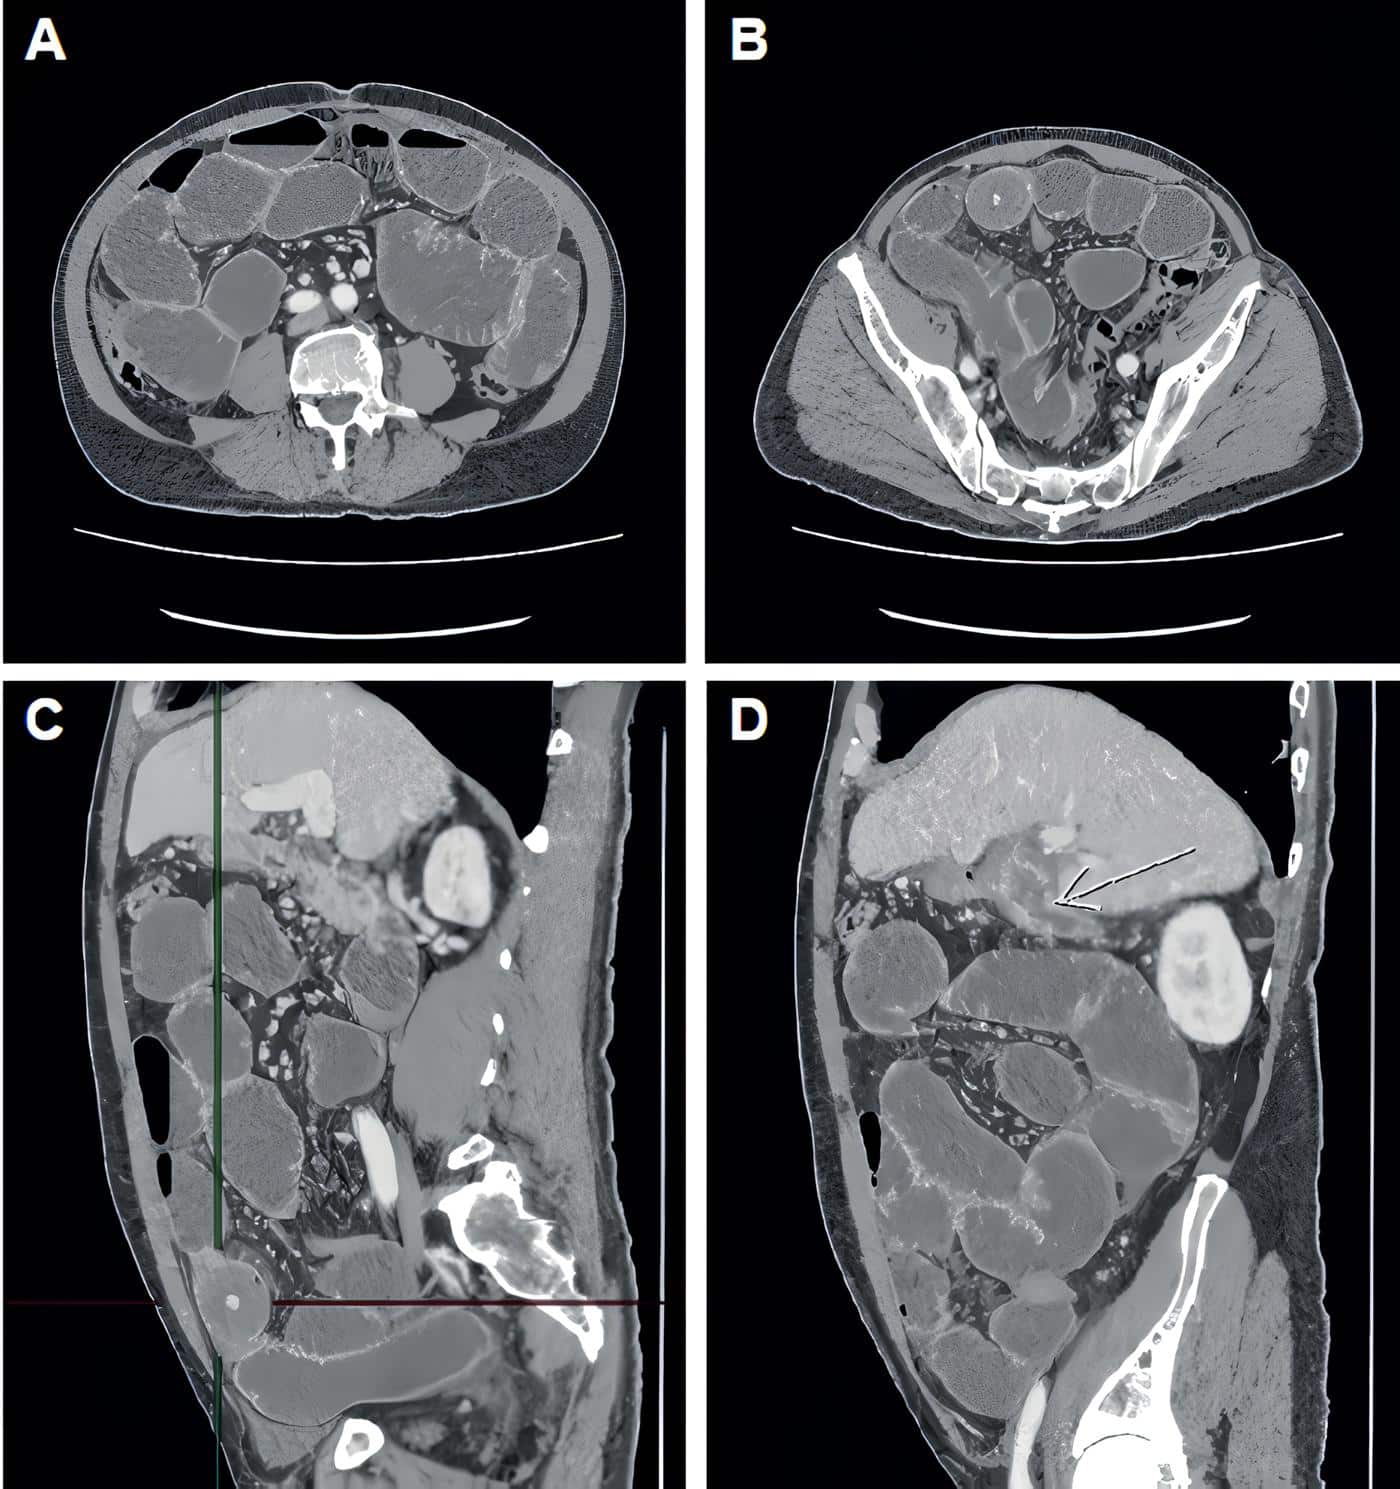

Ante la falta de respuesta después de cuatro días, lo remitieron a nuestra clínica y se realizó tomografía computarizada (Figura 1) donde se observó obstrucción intestinal mecánica del intestino delgado, con zona de transición en el íleon distal, causada por estructura redondeada que ocluye la luz intestinal, sin signos de sufrimiento de asas.

Figura 1. Imágenes de la tomografía computarizada de abdomen y pelvis. A. Dilatación difusa de asas intestinales delgadas de hasta 4,8 cm, sin signos de sufrimiento de asa ni neumoperitoneo. B. Zona de transición en el tercio distal del íleon; se aprecia imagen redondeada que corresponde al cálculo que ocluye la luz intestinal. C. Proyección lateral donde las líneas señalan la ubicación del cálculo que ocluye el íleon. D. Vesícula biliar escasamente distendida, con engrosamiento difuso y realce de sus paredes, con burbujas gaseosas en su interior; la flecha blanca muestra una comunicación de la vesícula con la segunda porción del duodeno y un aparente trayecto fistuloso hacia el margen anterior con colección subfrénica laminar. Asociado se observa aumento en la densidad y estriación de la grasa pericolecística. Fuente: Elaboración propia de las autoras.

Adicionalmente referían signos de colecistitis crónica, con trayecto fistuloso de la vesícula biliar a la segunda porción del duodeno y otro trayecto fistuloso que se comunicaba con colección laminar subdiafragmática, por lo que se hizo diagnóstico de íleo biliar y se decidió llevar el paciente a cirugía.